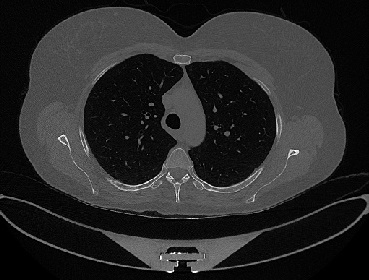

It should be mentioned that for explainability purposes [7, 8, 9], an anchor set was generated for the COV19-CT-DB database [5]. This included 11 anchors, each representing a respective 3-D CT scan obtained through an appropriate clustering procedure. Figure 2 shows a series of slices from a COVID-19 case, whereas Figure 3 shows a series of slices from a non COVID-19 case.